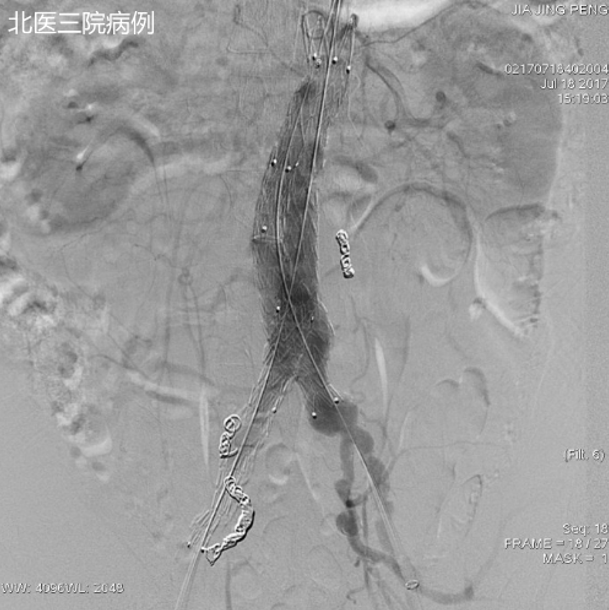

创新实践:瘤腔内注射凝血酶

自 2018 年起,我院在 EVAR 术中常规 预置导管至瘤腔,释放支架后立即 注入凝血酶,诱导瘤腔内生理性血栓形成。

初步成果(70 余例随访):

II 型内漏发生率显著降低;

动脉瘤囊回缩速度明显快于传统组(1 个月即可见显著缩小,6 个月更明显);

无过敏、异位栓塞或感染等并发症(得益于严格操作质控)。